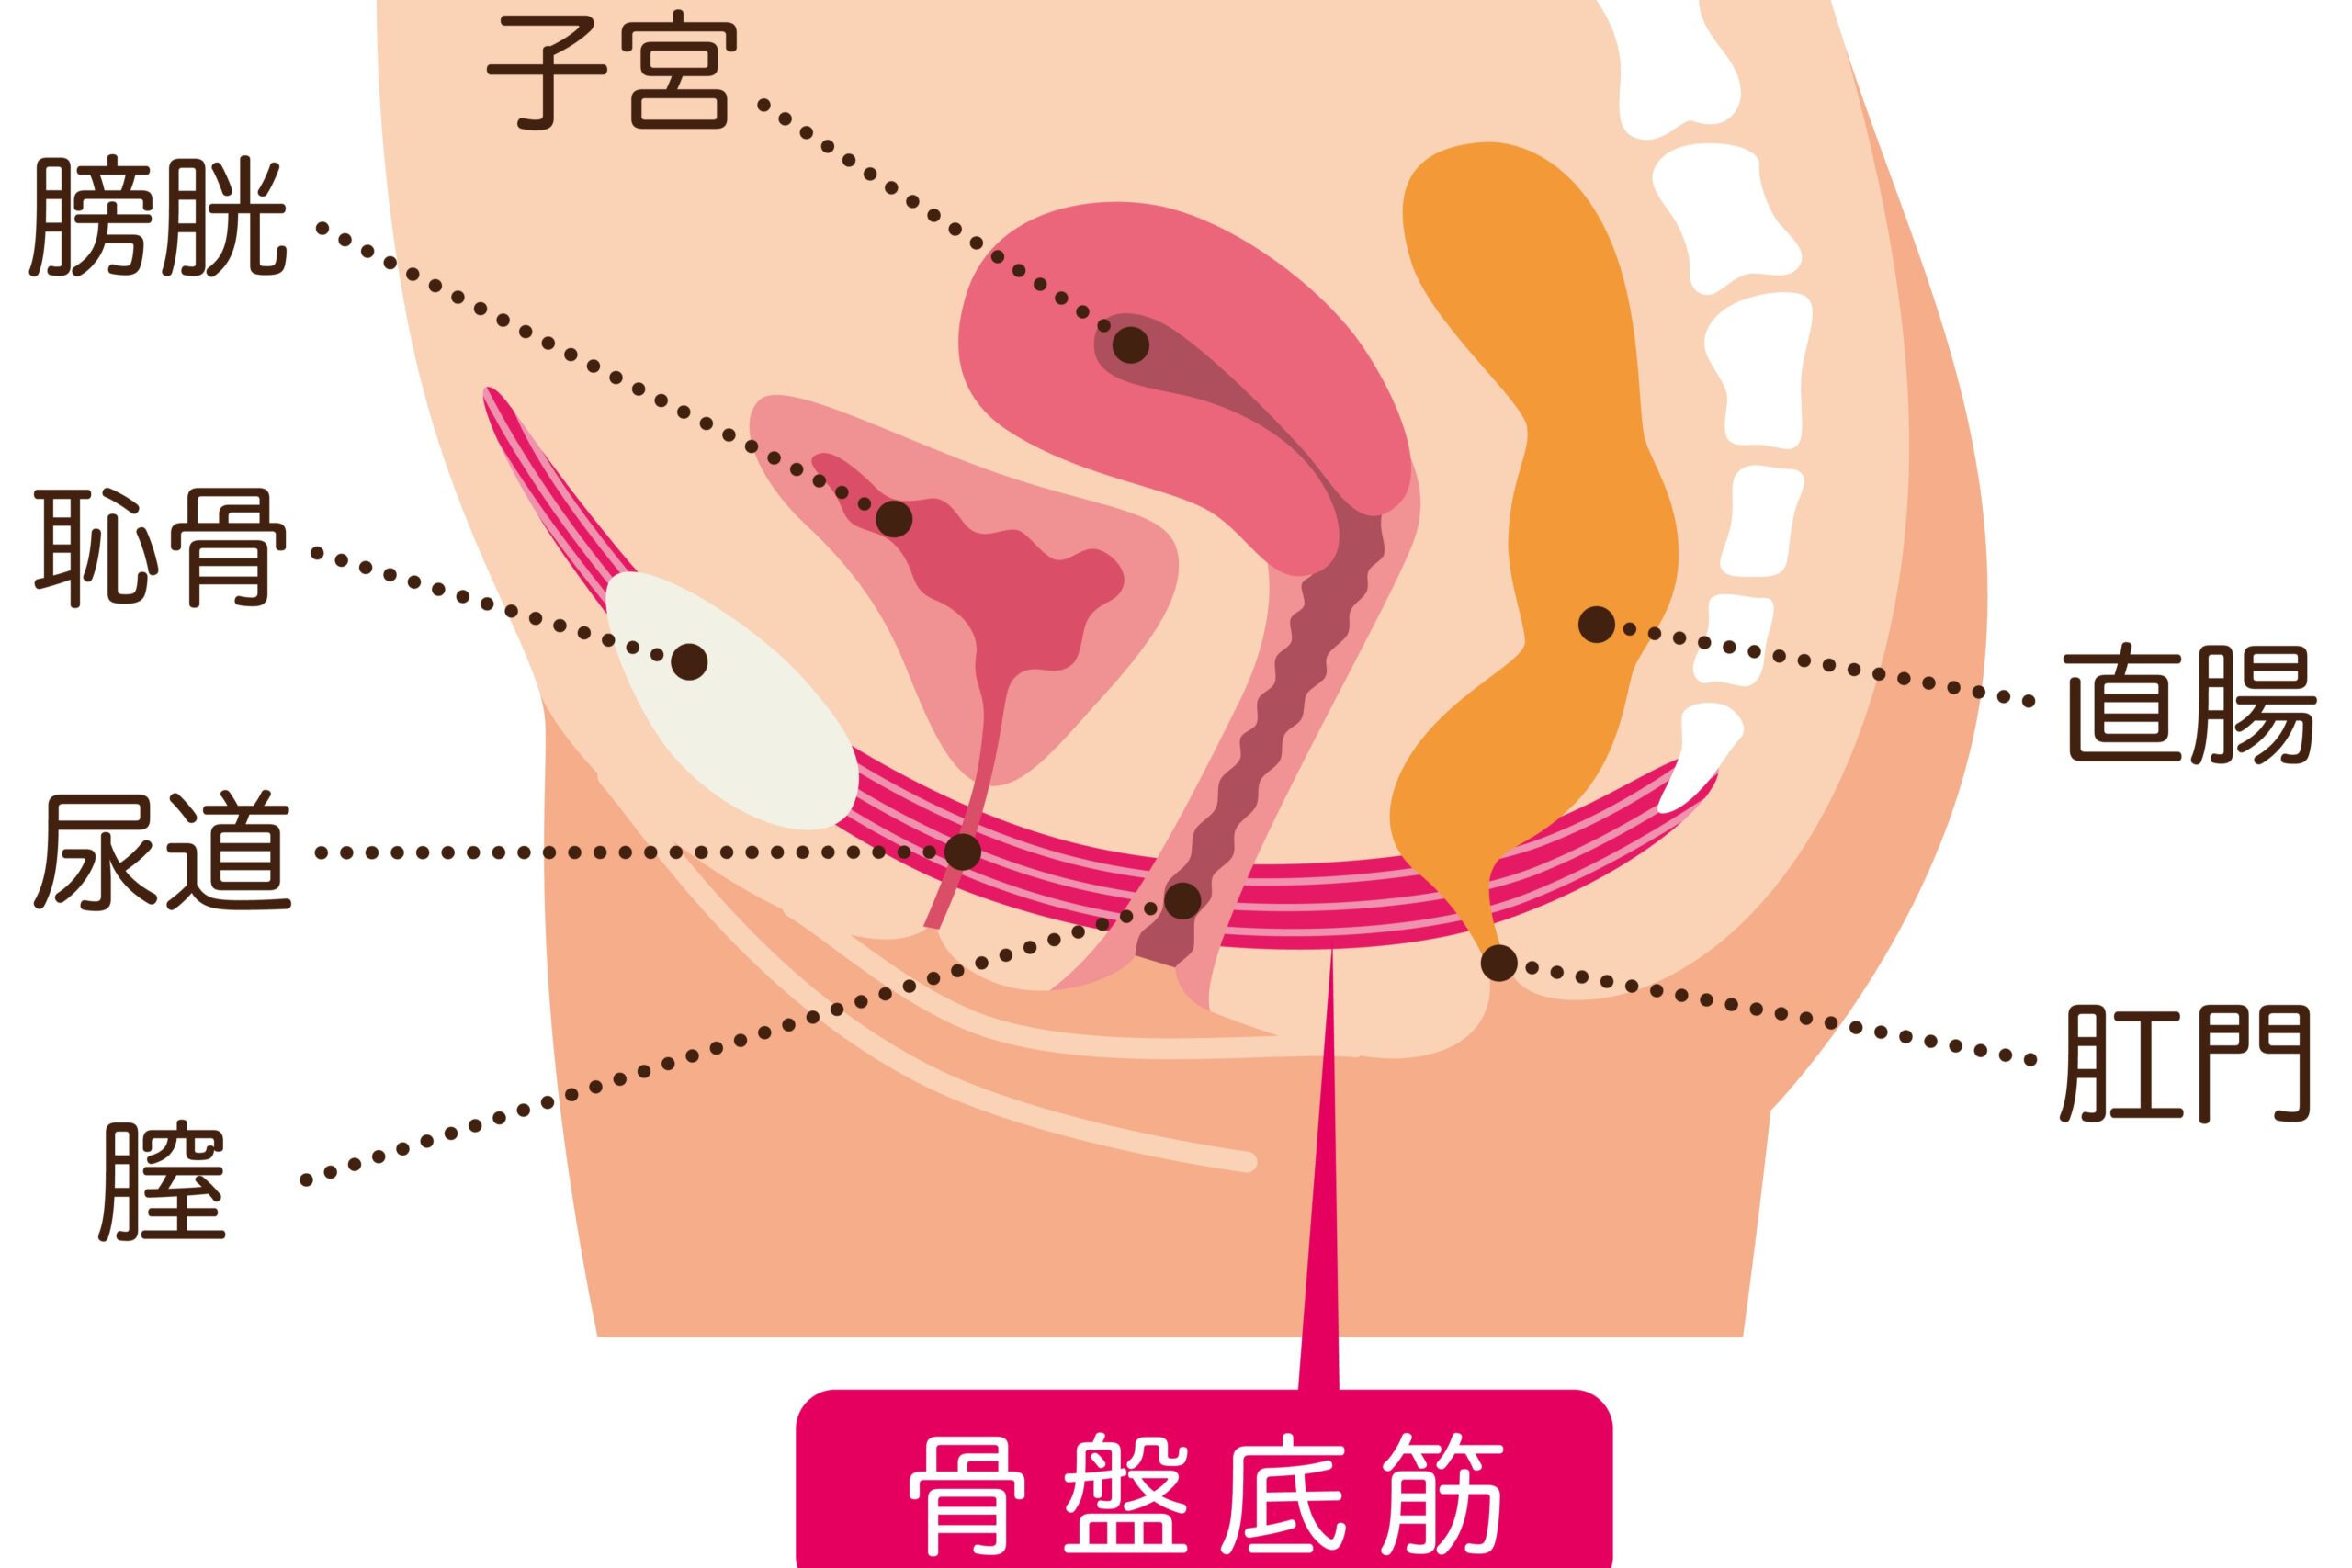

骨盤底筋群について

産後に尿もれに悩まされる方がいらっしゃいますが、その原因も骨盤周辺にある可能性が高いです。

骨盤を支えている「骨盤底筋群」が緩むと尿漏れに繋がると考えられています。

●骨盤低筋群の役割

骨盤底筋群とは骨盤の底の部分にある筋肉の集まりで、普段は膀胱や子宮、直腸などを下から支えていますが、妊娠中はさらにお腹の赤ちゃんの重みも支えてくれています。

骨盤底筋群には臓器を支えるほかに排泄のコントロールをする役割があり、尿意や便意を感じると出口を開いて排泄を促します。

●骨盤低筋群が緩むと尿漏れが起こる理由

妊娠・出産時には骨盤底筋群にも大きな負荷がかかってしまいます。

赤ちゃんの重みを支えるだけでも大きな負荷となりますが、さらに出産時には通常の約3倍ほど引き伸ばされるといわれ、出産後には弱って緩んでしまうことが多いです。

そのため骨盤底筋群が緩むと、支えていた膀胱や子宮の位置が下がり、尿道が不安定な状態になって尿漏れに繋がります。

女性は膀胱から骨盤底筋群までの距離が短く真っ直ぐなため、骨盤底筋群が緩むと尿漏れや頻尿になってしまうケースが多くみられます。

尿漏れの改善

排泄のコントロールをしている骨盤底筋群を鍛えなおすことで尿漏れの改善に繋がります。

膀胱も正しい位置に戻るため、頻尿のお悩みにも効果が期待できます。